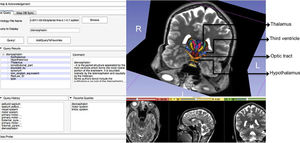

- 1.24 Design and Initial Evaluation of a Treatment Planning Software System for MRI-guided Laser Ablation in the Brain

Publication: Int J Comput Assist Radiol Surg. 2014 Jul;9(4):659-67. PMID: 24091853 Authors: Yeniaras E, Fuentes DT, Fahrenholtz SJ, Weinberg JS, Maier F, Hazle JD, Stafford RJ. Institution: Department of Imaging Physics, University of Texas MD Anderson Cancer Center, Houston, TX, USA. Background/Purpose: An open-source software system for planning magnetic resonance (MR)-guided laser-induced thermal therapy (MRgLITT) in brain is presented. The system was designed to provide a streamlined and operator-friendly graphical user interface (GUI) for simulating and visualizing potential outcomes of various treatment scenarios to aid in decisions on treatment approach or feasibility. Methods: A portable software module was developed on the 3D Slicer platform, an open-source medical imaging and visualization framework. The module introduces an interactive GUI for investigating different laser positions and power settings as well as the influence of patient-specific tissue properties for quickly creating and evaluating custom treatment options. It also provides a common treatment planning interface for use by both open-source and commercial finite element solvers. In this study, an open-source finite element solver for Pennes' bioheat equation is interfaced to the module to provide rapid 3D estimates of the steady-state temperature distribution and potential tissue damage in the presence of patient-specific tissue boundary conditions identified on segmented MR images. Results: The total time to initialize and simulate an MRgLITT procedure using the GUI was [Formula: see text]5 min. Each independent simulation took [Formula: see text]30 s, including the time to visualize the results fused with the planning MRI. For demonstration purposes, a simulated steady-state isotherm contour was correlated with MR temperature imaging (N = 5). The mean Hausdorff distance between simulated and actual contours was 2.0 mm, whereas the mean Dice similarity coefficient was 0.93. Conclusion: We have designed, implemented, and conducted initial feasibility evaluations of a software tool for intuitive and rapid planning of MRgLITT in brain. The retrospective in vivo dataset presented herein illustrates the feasibility and potential of incorporating fast, image-based bioheat predictions into an interactive virtual planning environment for such procedures. Funding: